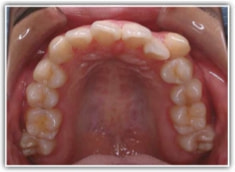

治療前

上下顎とも前突しており、叢生もあります。分析値からも抜歯対象症例です。